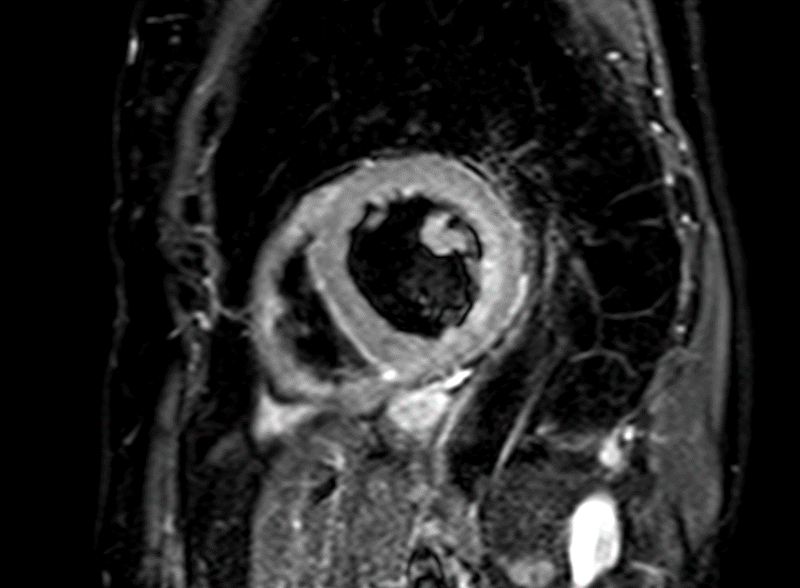

Vyšetření MRI srdce je bez známek edému myokardu a pozdního gadoliniového sycení (LGE) – nezjistilo tedy přítomnost zánětu, nekrózy, nahrazující fibrózy či infiltrace myokardu. Levá komora hodnocena při MRI jako mírně dilatovaná s EF 39 % (obrázek 2, video 4). Laboratorní vyšetření CK, LDH a železa, provedené k vyloučení dalších možných etiologií DKMP, bylo bez významné patologie, hodnota NT-pro BNP poklesla na 1 120 ng/ml.

Obr. 2. MRI srdce. 2A – nepřítomnost edému myokardu v T2 STIR TSE sekvenci v krátké ose, 2B – IR TFE sekvence v krátké ose – bez detekce pozdního sycení myokardu (LGE)